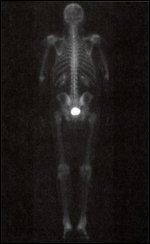

The physical examination revealed a healthy 72-year-old male. A penile prosthesis was in place, and the digital rectal exam showed a 25-g small fibrotic prostate with no nodularity. For this conference, a bone scan and ProstaScint scan were obtained.

Dr. Marcus Chen: The patient’s bone scan has a small linear focus of increased activity involving the left anterior pubic ramus, which is not suspicious for metastases (Figure 2). There are no other areas of focal increased uptake. The ProstaScint scan demonstrates activity in the region of the prostatic bed, suspicious for prostate cancer recurrence (Figure 3). There is no focal increased activity in the pelvic lymph nodes.